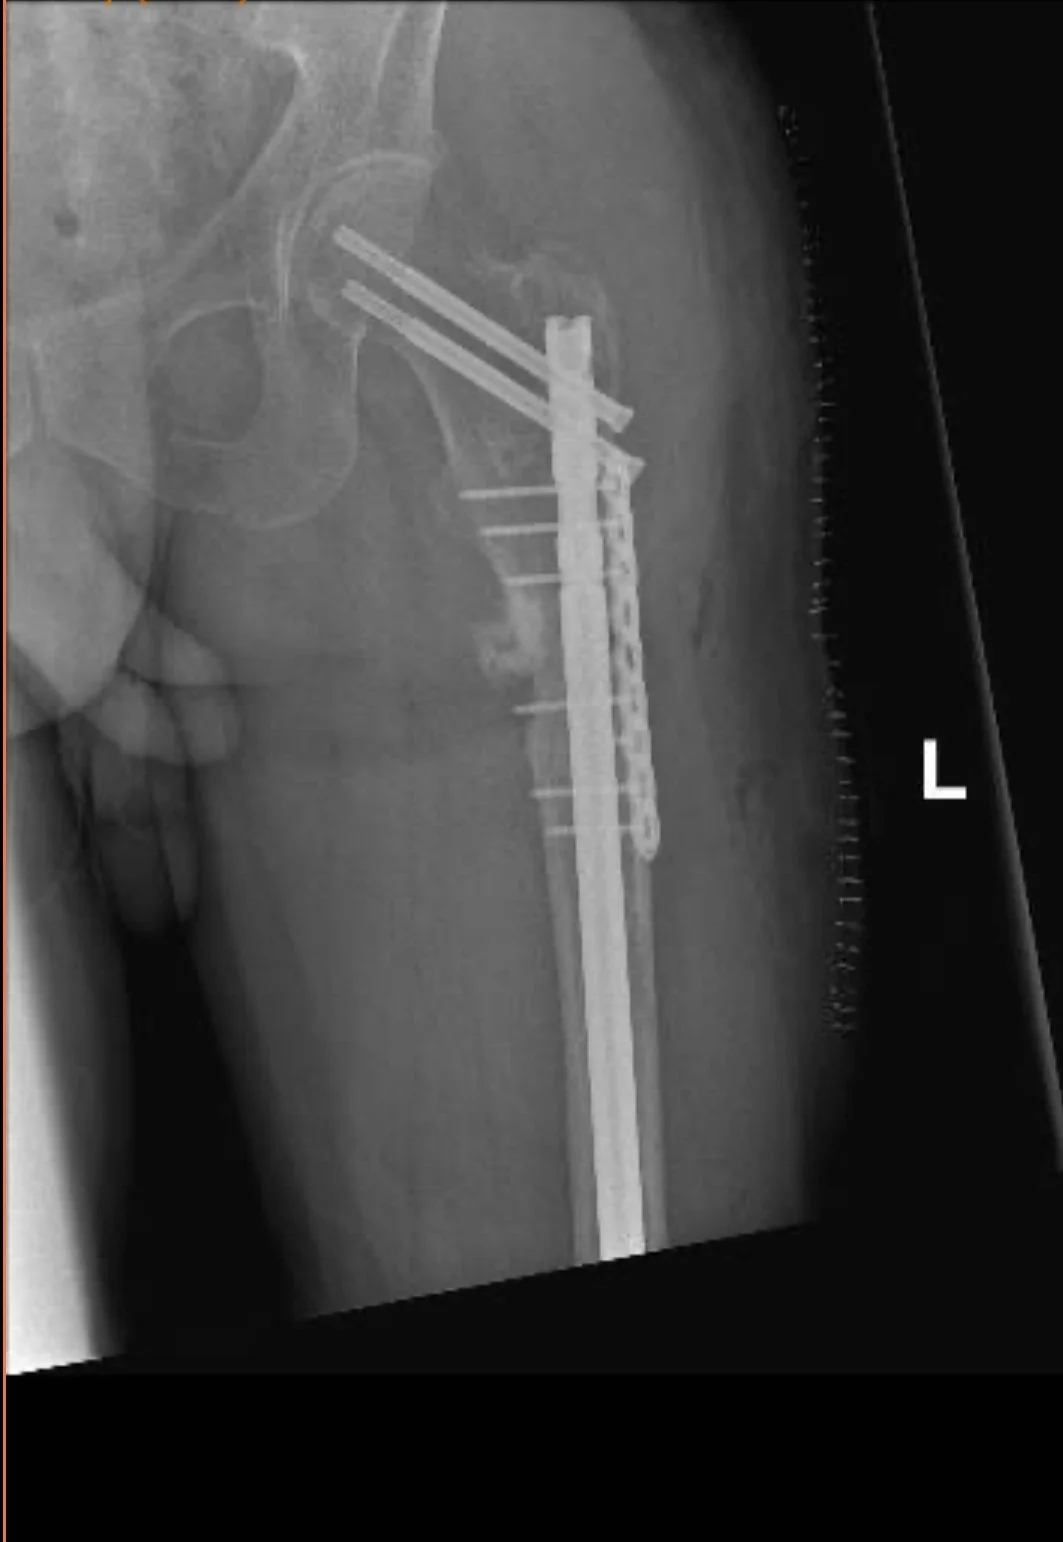

Fracture that did not heal

Fractures that fail to heal (non-unions) or heal improperly (malunions) can cause pain and limit mobility. I specialize in advanced techniques to restore proper alignment and healing.

Revision surgery for failed fracture fixation

If a previous surgery didn’t achieve the desired result, I offer second opinions and surgical solutions to help you recover and regain function.